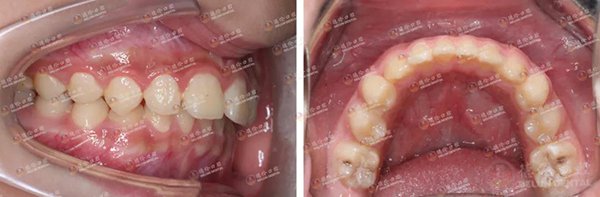

故事二中的主人公是三姐弟,大姐矫牙后认为李医生无论是医术还是医德都很nice,遂推荐弟弟妹妹也来矫牙。李医生说,弟弟主要的问题是下颌后缩,侧面观似“鸟嘴”样,前牙呈深覆盖,此番矫正的目的是将他的下颌往前导,改善他的面形。妹妹则是牙齿排列不齐所引起的咬合紊乱。

弟弟矫正前(左)与矫正后(右)对比照